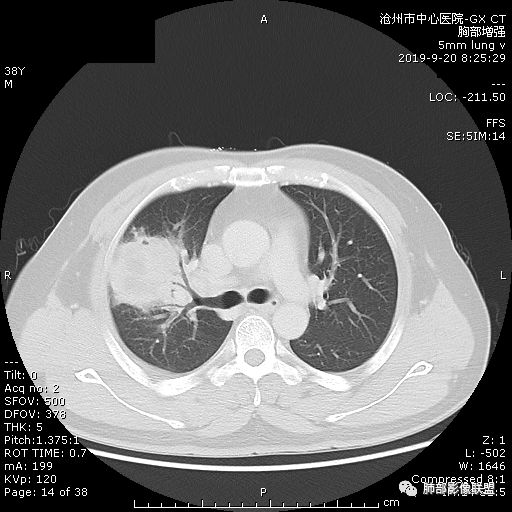

青年男性,肿瘤指标无异,右上中肺团片影,形态不规,跨叶生长,

病灶内见坏死,增强边缘强化,考虑炎性肉芽肿,TB,鉴别鳞。

年轻男性,咳嗽2月,痰中带血,胸痛,炎症指标稍高,肿标正常。影像,右肺上叶不规则团块影,浅分叶,伴边界不清磨玻璃影,从外周向内分布,局部胸膜增厚,病灶中央坏死,坏死边界尚清,空洞形成,空洞内壁光滑;考虑炎性肉芽肿性病变,结核可能,鉴别恶性肿瘤及真菌感染。病灶分布特点不考虑隐球。

右肺上叶不规则病灶,密度不均,有分叶,边缘不清,中央有坏死,坏死壁尚光滑,增强壁有强化,病灶有外朝内,整体收缩为主,慢性病程,考虑炎性病变,肺脓肿或者结核,淋巴结肿大,支气管截断,胸膜脂肪间隙变窄,加个鉴别恶性肿瘤。

近端支气管截断,非坏死区的强化特征,肺门区肿大淋巴结,所谓的“月牙铲”,这些强烈提示病变是癌;胸膜、相邻肋间肌的改变,提示是炎性改变;在癌与炎性肉芽肿之间,哪个占主导地位?是解决问题的关键;坏死区的形态,也支持炎性病变。

右肺上叶分叶状肿块(冠状位尤为明显),内见液化坏死,支气管截断,收缩力强,周围有片状影,右侧腋窝及纵隔淋巴结增大,增强有强化,定性恶性病变,脓肿形态及临床症状不符,暂排除。

右上肺占位,总体膨胀性生长,支气管截断,坏死明显,常规考虑鳞。

38岁,男性,慢性咳嗽2月,右胸痛8天,无发热;白细胞高,肿瘤标志物不高;右上肺不规则块状影,周围有磨玻璃影,边界清,整体有膨胀感,分叶,与胸膜糊墙,并见栽赃,增强肿块中央坏死,周边强化。综合考虑,考虑恶性,鳞癌可能。

右肺上叶不规则团块影,边缘欠清晰,增强扫描坏死区边界清晰,水平裂牵拉上移,考虑机化性肺炎并脓肿,鉴别:结核、肺癌。

38岁,男性,慢性咳嗽2月,右胸痛8天,无发热。白细胞高,肿瘤标志物不高。右上肺不规则块状影,周围有磨玻璃影,边界模糊,整体有膨胀感,分叶,与胸膜糊墙,可疑栽赃,增强肿块中央坏死,边界清,周边强化明显,强化区有低密度影,壁不规则,跨叶生长,支气管截断,伴支气管扩张,综合考虑腺癌

中年男性,咳嗽2月,伴胸痛8天,少许痰血,无发热中性粒明显增高,低氧,肿标不高,右肺上叶不规则实性肿块,深分叶,局部凹陷呈月牙铲改变,多坏死,多空泡,前段支气管分支似见堵塞,2R、4R、10R和7区淋巴结肿大。考虑肺癌可能,建议支气管镜活检

晨读病例,右肺上叶胸壁处占位,边缘分叶毛刺,收缩力强,多发坏死,远端支气管截断,不均匀性强化,血管穿行变窄,纵隔多发淋巴结肿大,考虑恶性肿瘤,首先考虑腺癌

膨隆、深分叶,支气管截断,叶裂推移,淋巴结肿大,均提示恶性可能;但毕竟年轻,血象高,内部坏死边界清晰,局部收缩感,提示感染可能,另外内部数个小空洞改变,是扩张支气管吗?需要连续层面看,如果是,就更支持感染。

右肺上叶不规则实性肿块,有膨胀有收缩,多坏死,空泡,右肺门淋巴结肿大,考虑肺癌,就是才38岁,太年轻了

晨读:青年男性,咳嗽痰中带血,亚急性起病,白细胞高,超敏高,CT示右肺上叶分叶肿块,内部坏死,病灶周围小结节,近端支气管通过,纵隔淋巴结肿大,综合考虑肉芽肿型结核较鳞癌可能大

晨读:右肺上叶不规则团块,深分叶,膨胀为主,有部分收缩,叶间裂牵拉上移,内多液化坏死,有支气管扩张,右肺上叶大支气管近端通畅,远端堵塞,说明肿块来源于外周,纵隔及右肺门淋巴结肿大,胸膜糊墙为主,年轻人,肿标不高,炎性指标高,综合考虑炎性肉芽肿放前面脓肿,结核,肿瘤放后面。

良孑: 晨读病例,右上肺不规则实变,边界模糊,内可见多发坏死灶,腔内坏死壁厚薄不均,有支气管截断,强化时病灶内血管受累,右肺门淋巴结肿大,从影像上看恶性鳞癌征象较多,但病变明显强化,且坏死壁是均匀强化,炎性标志物高,患者年龄较轻,病史较长,病灶内多个坏死液化灶且内缘光整,综和判断,首先考虑亚急性肺脓肿,其次考虑鳞癌

病灶垮叶,强化明显,病灶内见坏死、空泡,周围模糊,考虑放线菌病?鉴别鳞癌

青年男性,右肺上叶肿块,分叶,明显膨隆,内见空洞与支气管相通,增强环形强化,中心液化坏死。实验室鳞癌指标不高。考虑:1,结核,2,肺脓肿。鉴别鳞癌。

中年男性,咳嗽2月病史伴胸疼。白细胞及中性粒细胞高。右上肺团块影,边缘平直内收,与胸膜宽基底相连,胸膜肥厚,肿块内多灶性坏死,有空泡征,支气管进入,走行自然,近端有阻塞,考虑感染性疾病,肺脓肿。但是有深分叶,鳞癌合并感染也不排除。

右肺上叶不规则病灶,密度不均,有分叶,边缘不清,中央有坏死,坏死壁尚光滑,增强壁有强化,考虑肺脓肿或者结核,但是淋巴结肿大,支气管截断,不除外肿瘤。